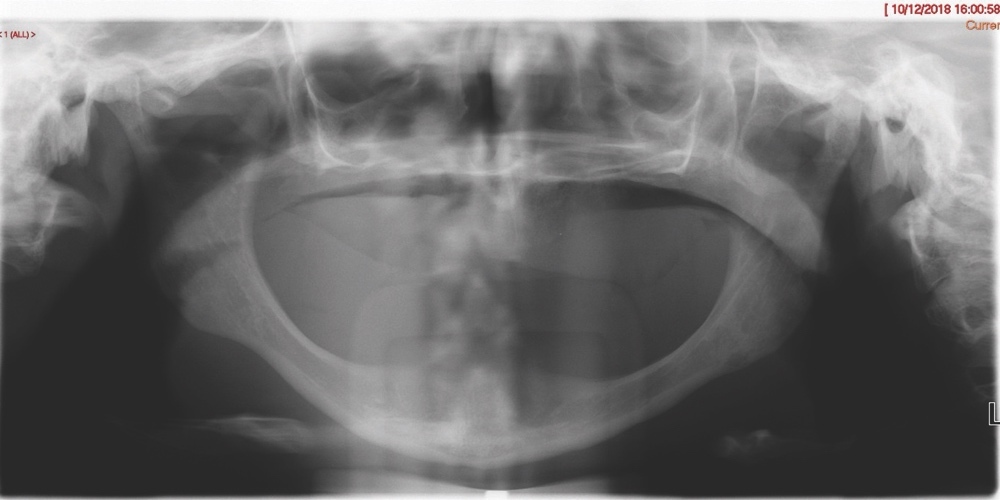

Intra-orally, the patient presented with an atrophic mandible and maxilla (Cawood and Howell13 Class VI and V, respectively) and was edentate (Figures 2 and 3). An orthopantomogram (Figure 4) confirmed the clinical findings and also demonstrated the proximity of the reduced maxillary ridge height to the maxillary sinuses.

Six months after the first surgical procedure, a CBCT scan was taken in order to assess the position of the mandible to the maxilla and MDT discussions were repeated. Radiographic evaluation revealed appropriate healing with stable bone height. The patient then underwent the second stage of her surgical management, and transzygomatic implants (maxilla) and conventional dental implants (mandible) were inserted.